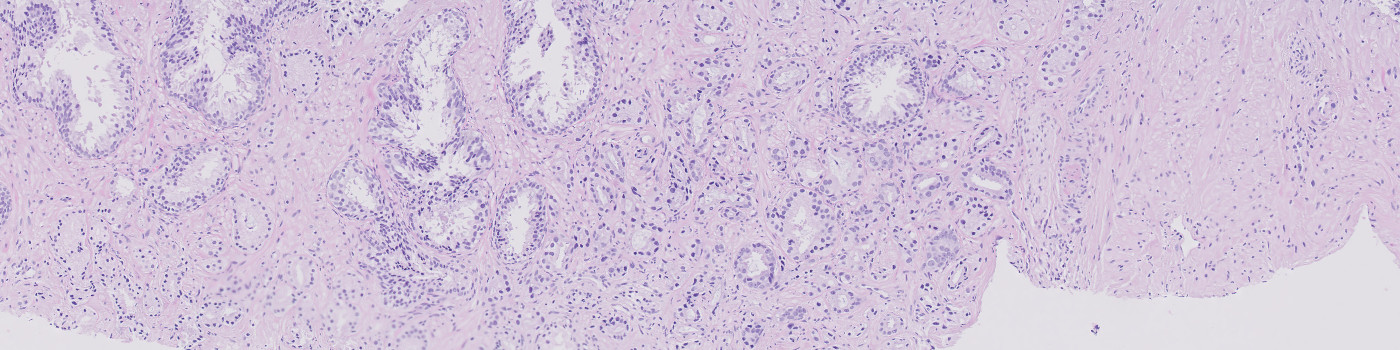

Image of H&E stained needle biopsies from prostate tissue to be analyzed.

Developed for tumor detection in H&E stained prostate tissue

This APP utilizes AI/deep learning and has been trained to detect tumors in images of prostate tissue stained with H&E. The deep learning architecture enables the APP to recognize complex structures and interpret the tissue context when analyzing an image, making it an efficient tool for detecting even small tumors that are not easily noticed. The APP does not grade the tumors.